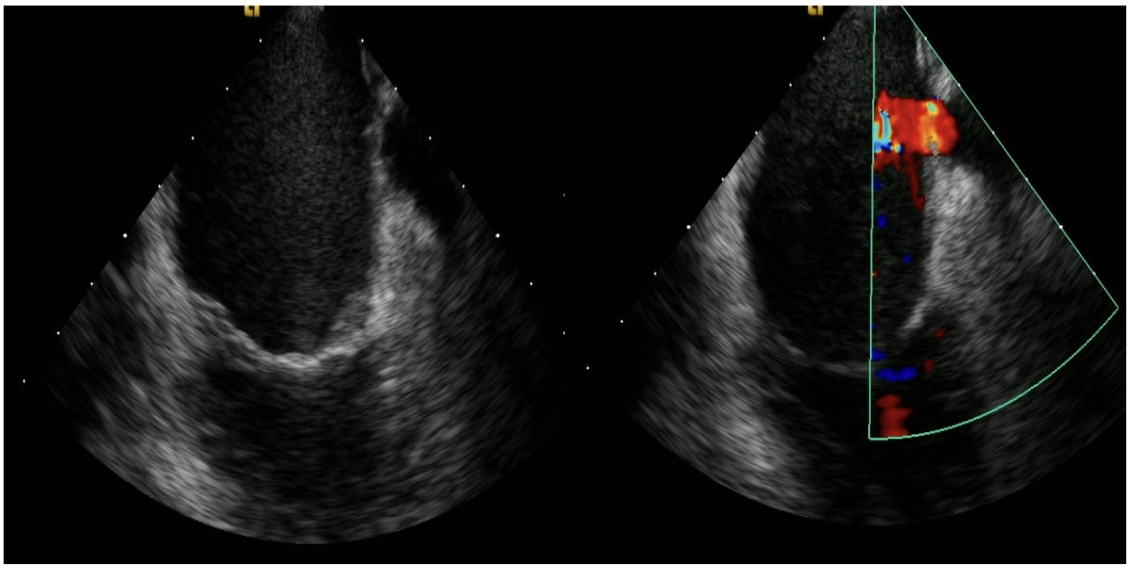

Case 1: A 57-year-old male with persistent AF and dilated cardiomyopathy underwent TEE prior to pulmonary vein isolation. TEE revealed a fenestrated membrane at the ostium of the LAA, causing partial obstruction evidenced by a well-defined jet into the left atrium. The fenestrated membrane was well demonstrated by advancing intra-cardiac echocardiogram (ICE) probe into the left atrium (Figure 1).